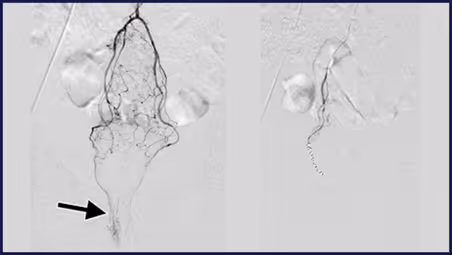

HAE is a minimally invasive procedure performed by an interventional radiologist. Instead of surgically removing haemorrhoids, the technique works by blocking the blood supply to the haemorrhoidal arteries, causing the swollen tissue to shrink over time.

Using imaging guidance, the doctor inserts a tiny catheter (usually through the wrist or groin) and places micro-coils or particles to reduce abnormal blood flow. The result is reduced swelling, bleeding, and discomfort—without traditional surgical incisions.